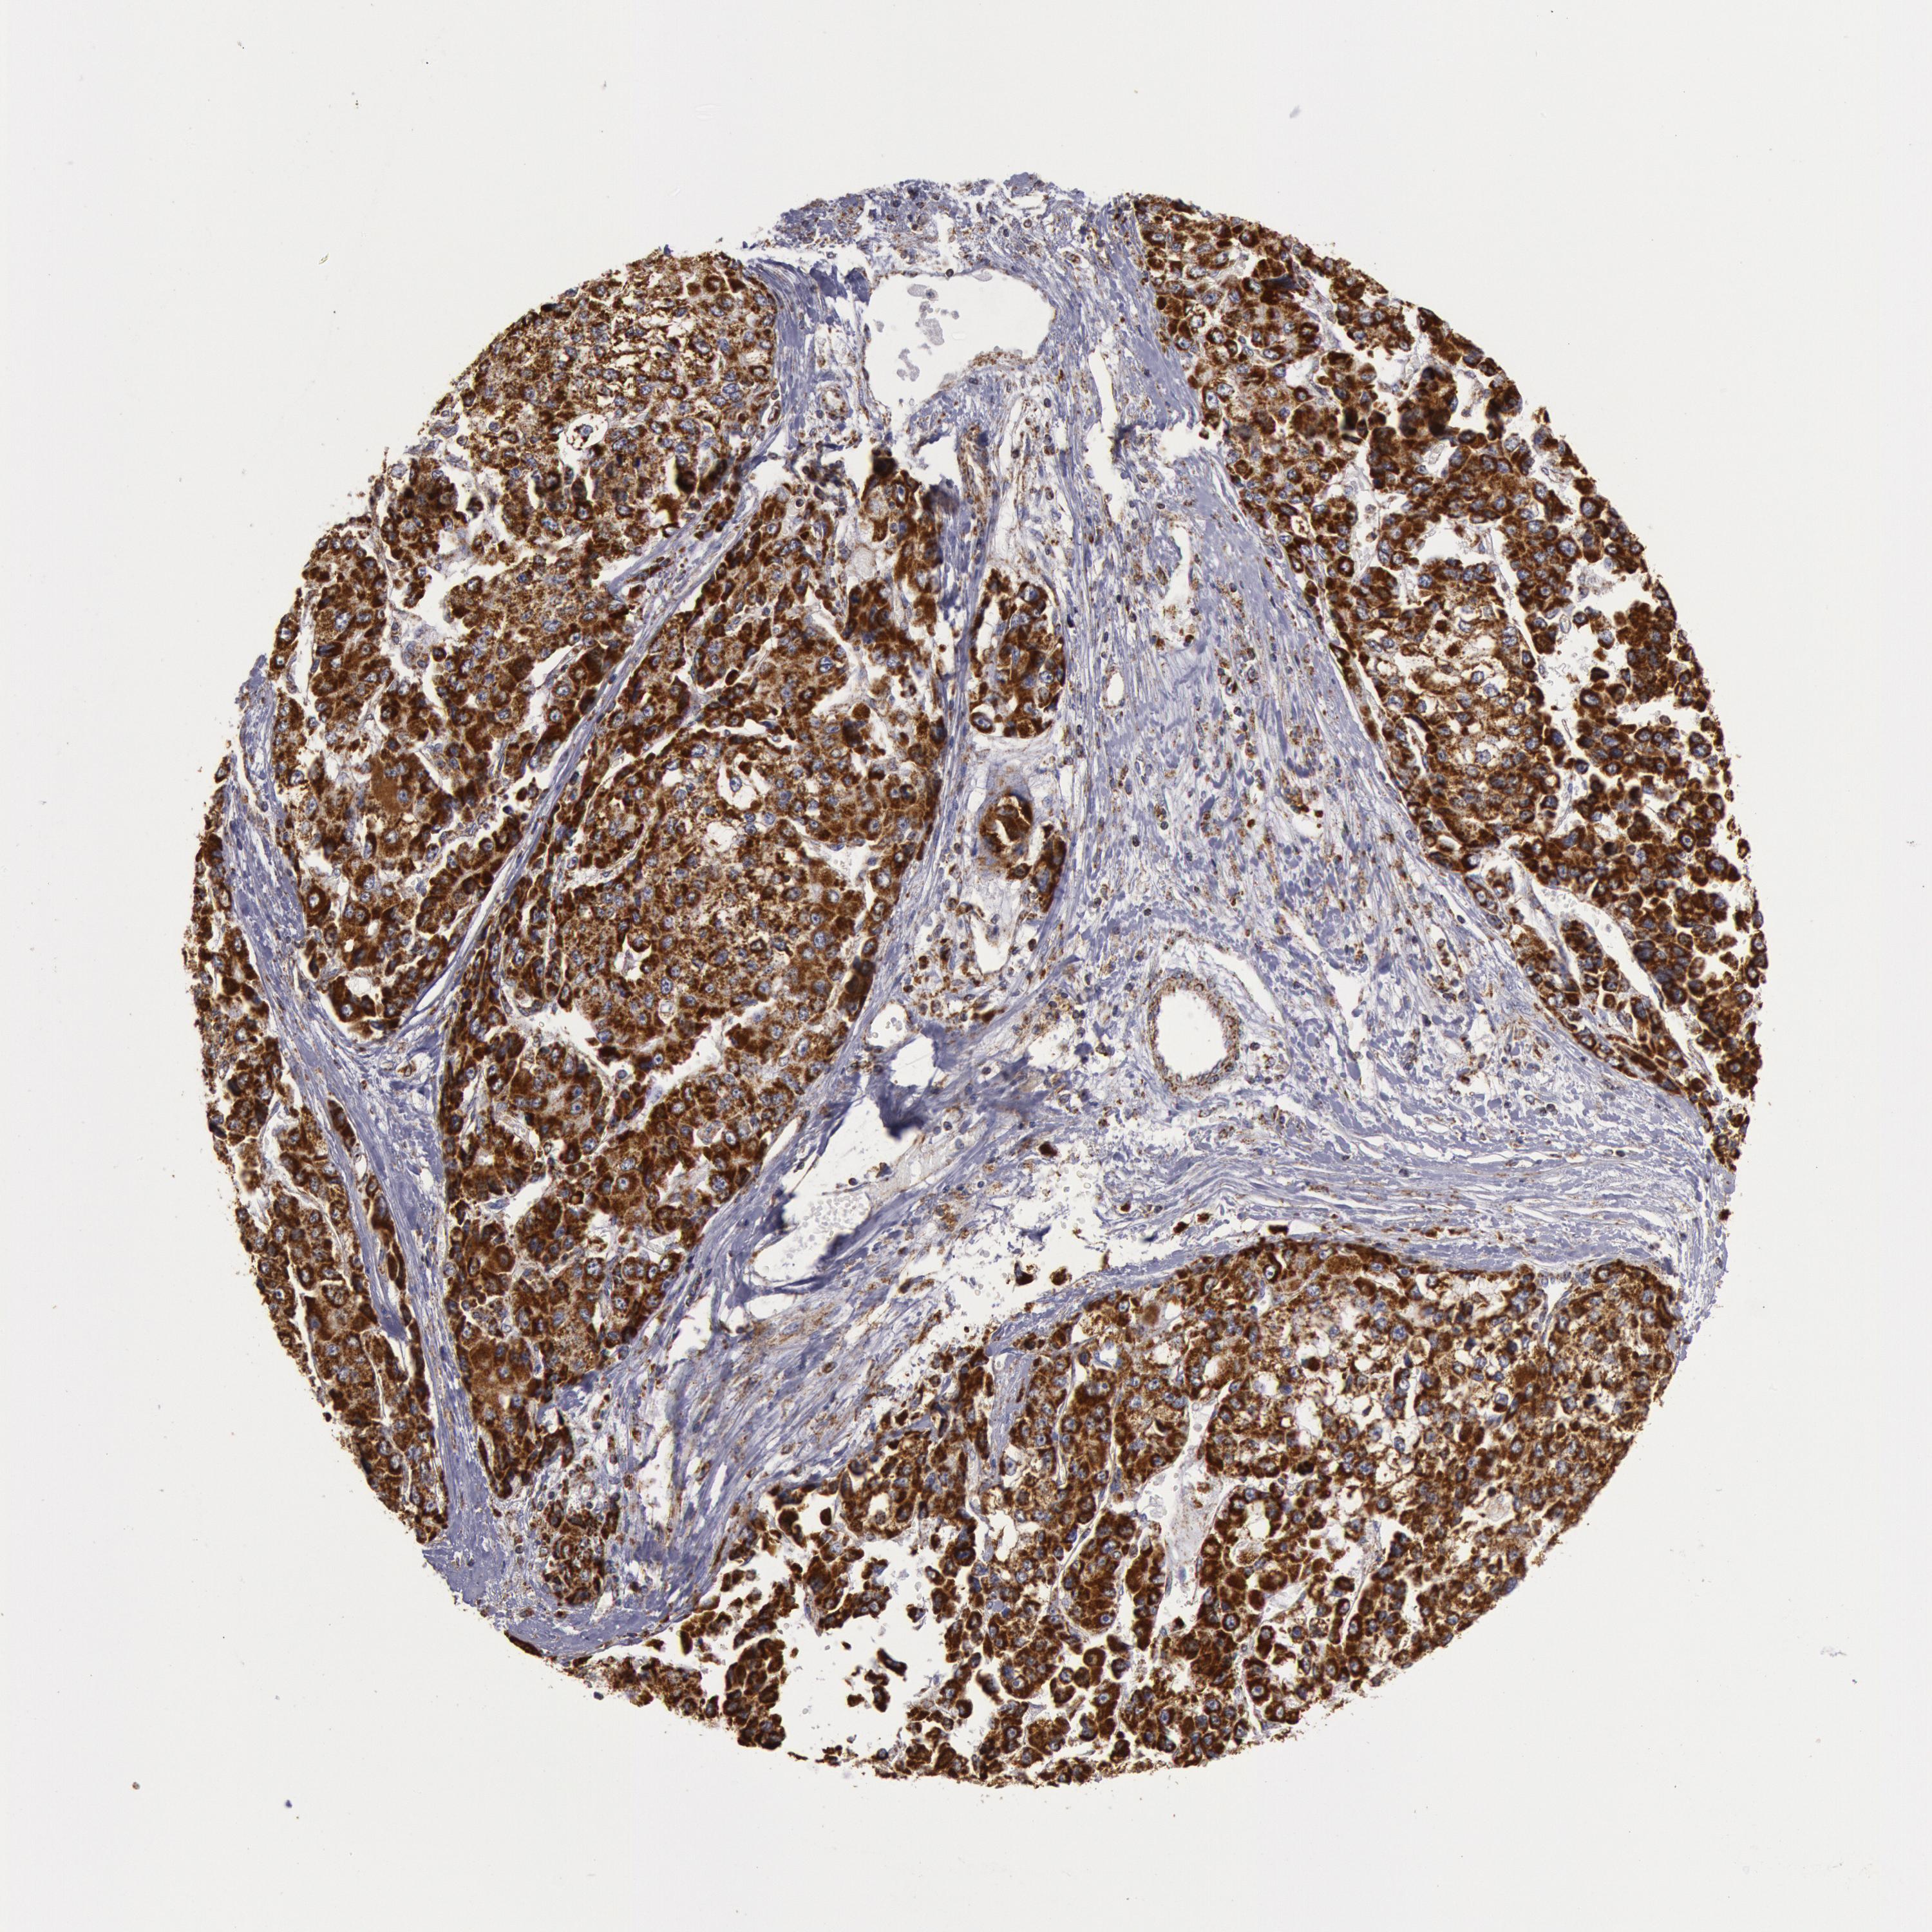

LIVER CANCER - Protein expressioni

A mouse-over function shows sample information and annotation data. Click on an image to view it in a full screen mode. Samples can be filtered based on level of antibody staining by selecting one or several of the following categories: high, medium, low and not detected. The assay and annotation is described here.

Note that samples used for immunohistochemistry by the Human Protein Atlas do not correspond to samples in the TCGA dataset.

Antibody stainingi

Antibody staining in the annotated cell types in the current human tissue is reported as not detected, low, medium, or high, based on conventional immunohistochemistry profiling in selected tissues. This score is based on the combination of the staining intensity and fraction of stained cells.

Each image is clickable and will lead to virtual microscopy that enables deeper exploration of all samples and also displays staining intensity scores, fraction scores and subcellular localization as well as patient and tissue information for each sample.

Antibody HPA001247

Staining

High

Medium

Low

Not detected

Intensity

Strong

Moderate

Weak

Negative

Quantity

>75%

75%-25%

<25%

None

Location

Nuclear

Cytoplasmic/membranous

Cytoplasmic/membranous,nuclear

Carcinoma, Hepatocellular, NOS

Cholangiocarcinoma